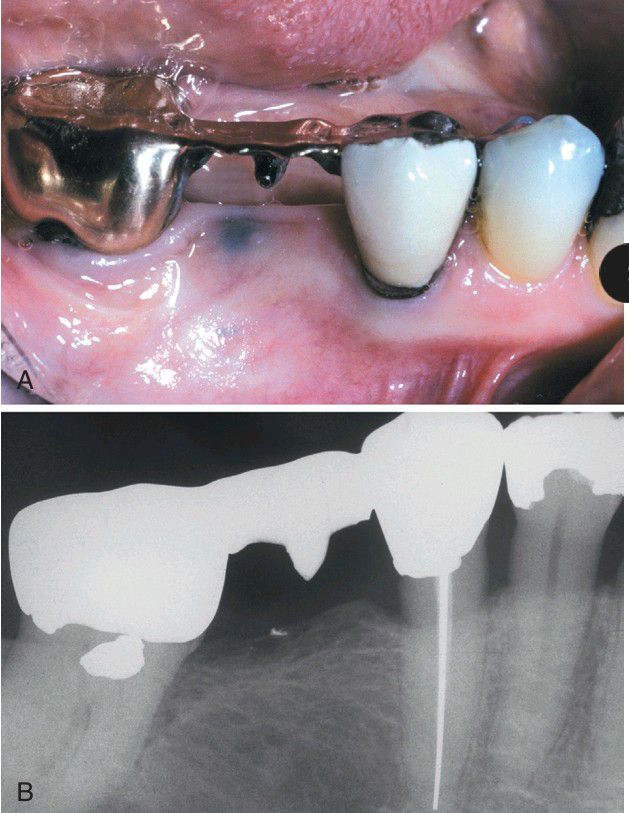

Amalgam Tattoo

. A, Area of mucosal discoloration of the mandibular alveolar ridge immediately below the bridge pontic. B, Radiograph of the same patient showing radiopaque metallic fragment present at the site of mucosal discoloration.